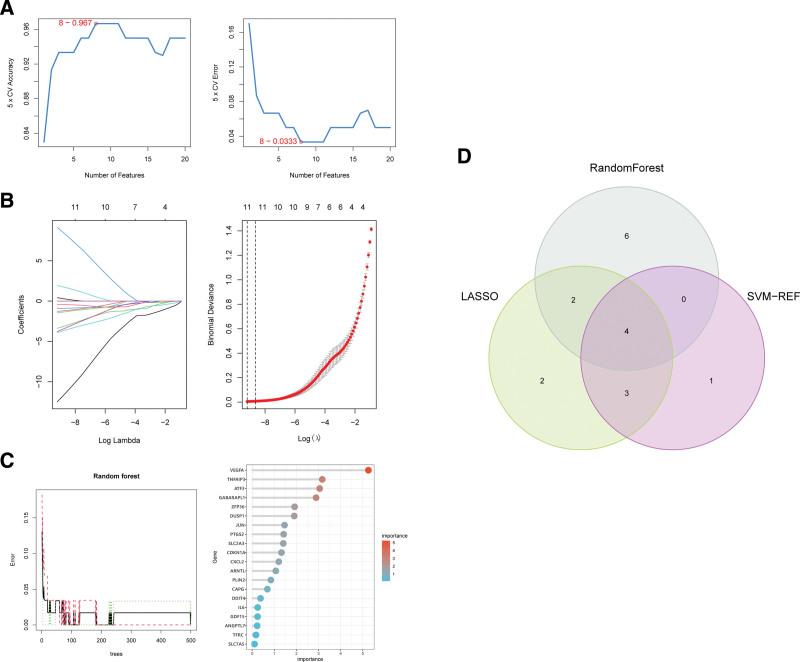

3.3. Selection of feature genes

Three ML algorithms simultaneously employed for the identification of feature genes, SVM-RFE algorithm selected 8 genes from ferroptosis-related hub genes (Fig. 4A), LASSO algorithm identified eleven genes (Fig. 4B) and RF algorithm provided ten genes (Fig. 4C). Taking the intersection of the results of genes selection by the 3 ML methods, we ultimately obtained 4 feature genes: GABARAPL1, TNFAIP3, ARNTL, and JUN (Fig. 4D). Followed correlation analysis among the expression of the 4 genes all showed positive correlations, suggesting an underlying synergy of the biological impact of the 4 genes (Figure S1, http://links.lww.com/MD/K714). We then performed difference analysis in merge data and reconfirmed the down-regulation of expression of the 4 genes in OA (Fig. 5A). The area under curve (AUC) of ROC analysis was 0.974 for GABARAPL1, 0.841 for ARNTL, 0.962 for TNFAIP3, and 0.968 for JUN (Fig. 5B).

As a foremost and novel branch of artificial intelligence, machine learning is often employed to make predictions by analyzing existing data and is commonly used in the analysis of molecular biological data.[39] We conducted feature selection by integrating multiple ML algorithms provided robust gene markers which may greatly improve the diagnostic performance and increase the efficiency of the test because multiple ML took more impact, factors and more complex non-liner correlation into account. By the combination of the 3 ML algorithms, we ultimately identified 4 feature genes GABARAPL1, TNFAIP3, ARNTL, and JUN for further exploration. Among the 3 ML algorithms for feature selection, SVM-REF and LASSO conducted cross validation to avoid overfitting. Followed ROC analysis of the 4 feature genes showed favorable discriminative and predictive abilities, suggesting the biological impact and potential diagnostic value of the 4 feature genes for OA. These results were validated in GSE1919 dataset. Our study also showed that GABARAPL1, TNFAIP3, and JUN was downregulated in OA synovia based on the results of RT-PCR.